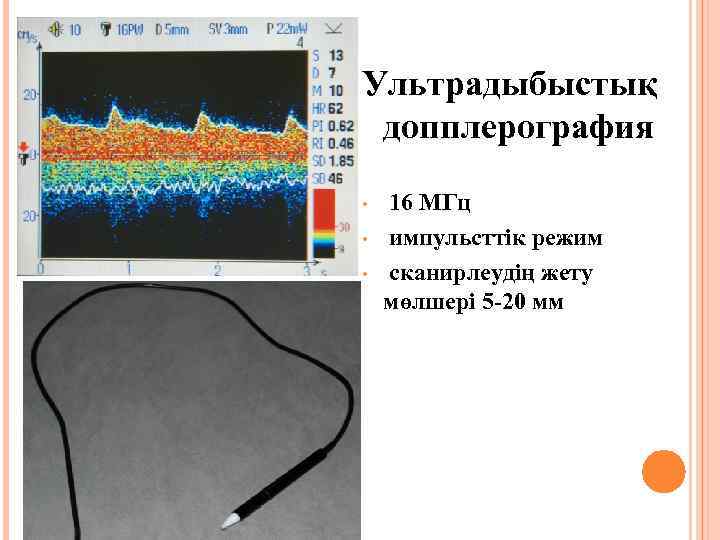

УЛЬТРАДЫБЫСТЫҚ ДОППЛЕРОГРАФИЯ «Ангиодин – ПК» -аппараты

Ультрадыбыстық допплерография • • • 16 МГц импульсттік режим сканирлеудің жету мөлшері 5 -20 мм